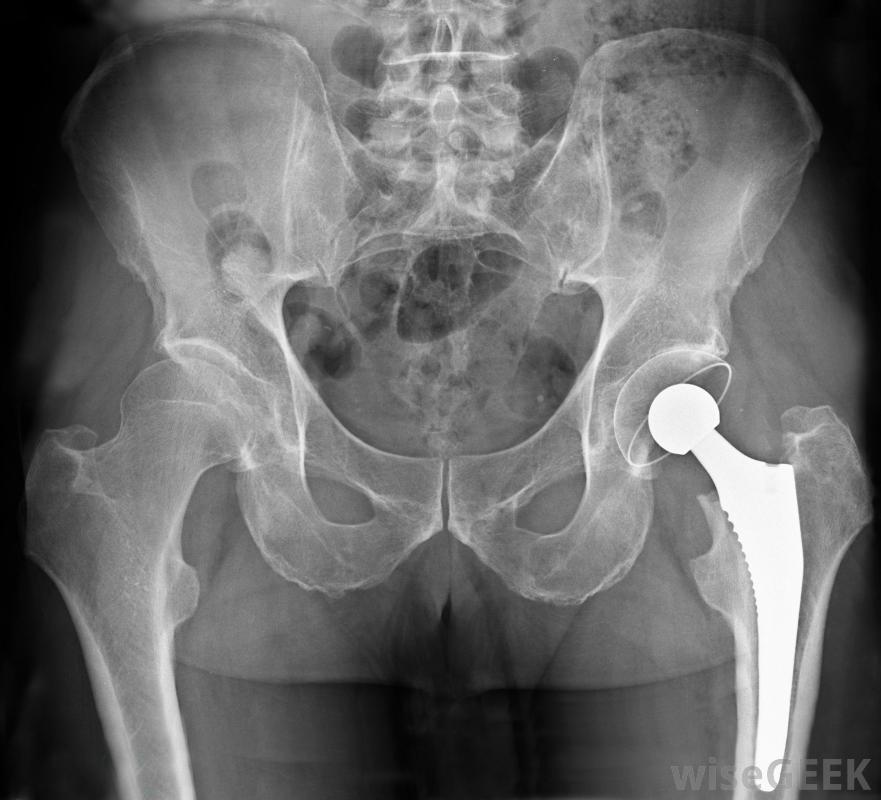

骨水泥用于髋关节置换手术,将腿部股骨头固定在人工髋关节上骨水泥的性能由聚甲基丙烯酸甲酯(PMMA)组成。这种塑料也用于不易破碎的玻璃、浴缸,它是髋关节置换术中的一种标准粘合剂,用于将腿的股骨头连接到人工髋关节上。用这种物质进行的髋关节置换手术通常可以使用几十年